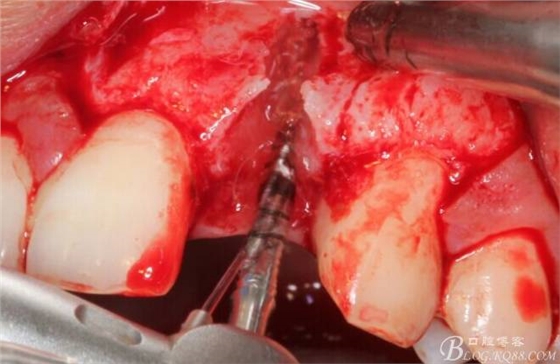

徹底掻刮。

有老師問我,為什么不在此時同期植骨同期植入植體?我的觀點是:不要一次做太多事情,做得越多風(fēng)險越高。再說,此時軟組織不健康,沒有健康的軟組織如何能保證GBR的成功?所以,我僅放了一塊膠原蛋白就縫上了。